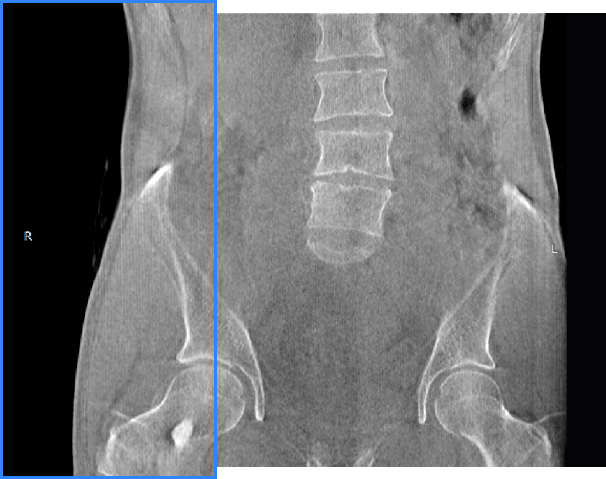

FOV最大350mm

支持双腿或双侧髋关节扫描 | 方便对比,降低漏诊误诊

FOV 250mm

FOV 350mm